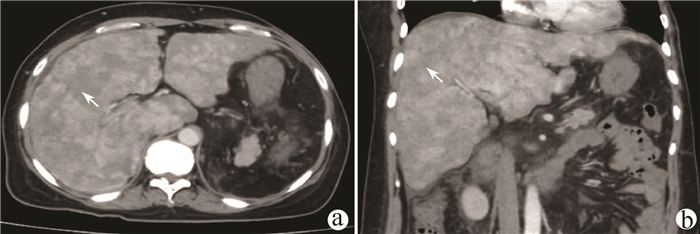

Intraductal papillary neoplasm of the bile duct with atrophy of the hepatic left lateral lobe: A case report

Jingzhong OUYANG, Ruili ZHU, Yanzhao ZHOU, Zhengzheng WANG, Xun CHEN, Jinxue ZHOU, Qingjun LI

2021, 37(7): 1676-1678. DOI: 10.3969/j.issn.1001-5256.2021.07.041

Abstract(964) HTML (382) PDF (2403KB)(58)

Abstract: